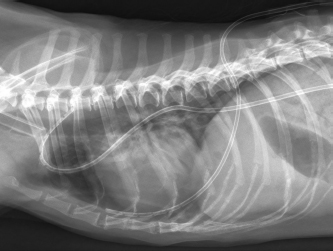

A 12-year-old male neutered Shih Tzu with a body weight of 6 kg was presented to the emergency service of the Small Animal Clinic of the Freie Universität of Berlin due to acute onset of respiratory distress without any history of trauma or preceding respiratory symptoms. At presentation, the dog showed mild dyspnea with a respiratory rate of 40 breaths per minute with increased abdominal effort but reduced thoracic motion. Auscultation of the thorax revealed damped respiratory sounds on both sides without alteration in heart sounds indicating a pneumothorax. All other parameters of the general examination were within normal range. Bilateral thoracocentesis was performed until dyspnea had significantly improved, evacuating 250 ml air in total dyspnea resolved after initial thoracocentesis, and a dorso-ventral thoracic radiograph was taken. Subsequent radiography of the chest in the dorso-ventral projection showed marked retraction and increased radiopacity of the right and left lung lobes, confirming severe bilateral pneumothorax and the tentative diagnosis of spontaneous bilateral pneumothorax was made (Fig. 2). No radiographic signs of bullae or other pathologic conditions such as lung tissue masses could be detected on the dorso-ventral view. Further radiographic imaging was suspended to reduce the patient’s stress level and to prevent possible recurrence of dyspnea. Besides mild thrombocytosis (742 103/µl; range 165–400), no abnormalities were found on complete blood count and blood chemistry analysis.

Fig. 2. Radiographic image of the thorax in dorso-ventral view with the dog in sternal recumbency after thoracocentesis for initial patient stabilization. Severely collapsed lung lobes with retracted lung lobe margins are visible on both sides.